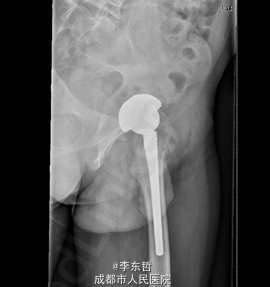

患者男,31岁,因“左股骨头股骨颈骨折切开复位内固定术后1+年”入院。患者1+年前因车祸致左股骨头、颈粉碎性骨折伴坐骨神经损伤于我院就诊,于我院行左股骨头股骨颈骨折切开复位空心钉+可吸收镙钉内固定术,术后恢复良好出院。术后8月后扶双拐活动。7月前患者无明显诱因出现左髋部疼痛,以负重时为重,后患者只能扶双拐活动。现患者为进一步治疗入我院。患病以来患者精神可,食欲可,睡眠可,大小便未见明显异常,体重无明显变化。

查体:T:36.2oC,P:80次/分,R:20次/分,BP:112/74mmHg。神志清楚,无病容,皮肤巩膜无黄染,全身浅表淋巴结未见肿大。颈静脉搏动、心界正常,心律齐,各瓣膜区未闻及杂音。胸廓未见异常,双肺叩诊呈清音,双肺呼吸音清,未闻及干湿啰音及胸膜摩擦音。腹部外形正常,全腹柔软,无压痛及反跳痛,腹部未触及包块,肝脏肋下未触及,脾脏肋下未触及,双肾未触及。双下肢无水肿。视:左髋外侧可见一约30cm手术瘢痕,其上可见一点状结痂,左腿较右腿短缩,左腿肌肉较右腿萎缩,步态异常。触:左髋部无压痛,左腿外侧感觉异常,以左膝外侧为重,左髋外侧叩击痛,左足背动脉搏动未扪及异常。动量:左下肢较右下肢短缩约3cm,左髋关节活动受限,其余各关节未见明显异常。

入院诊断:左股骨头股骨颈粉碎性骨折切开复位内固定术后坏死;积极完善术前检查及准备后行关节置换术。